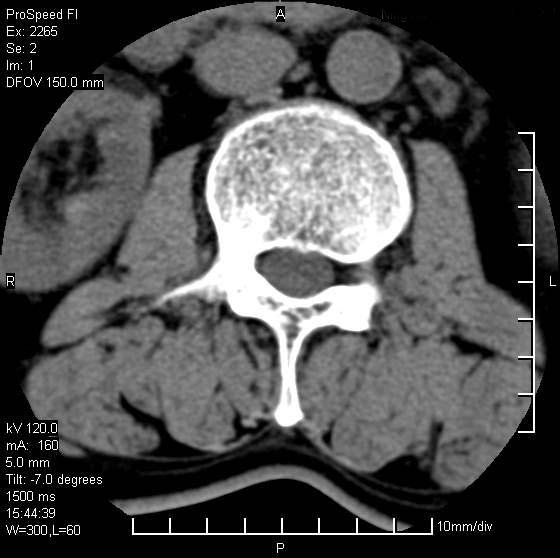

以下是引用qiushi在2007-8-22 17:26:00的发言:[br]没骨窗![br] 1、 l5~s1间盘膨出伴轻度突出(中央型)、变性。[br] 2、l4~5间盘膨出伴突出(右侧远外侧型)。[br] 3、l3~4间盘膨出。[br] 4、腰椎退行性变。[br]

以下是引用随缘的人在2007-8-22 20:56:00的发言:[br]腰椎退行性变:1。l4/5,l5/s1膨出[br] 2。l5/s1间盘退行性变 [br] 3。腰椎骨质增生

以下是引用liaizhi在2007-8-22 22:13:00的发言:[br]1,l4-5锥间盘膨出,2,l5-s1椎间盘膨出并退变(椎间盘呈真空征);3,血管瘤(椎体骨小梁稀疏粗大)?